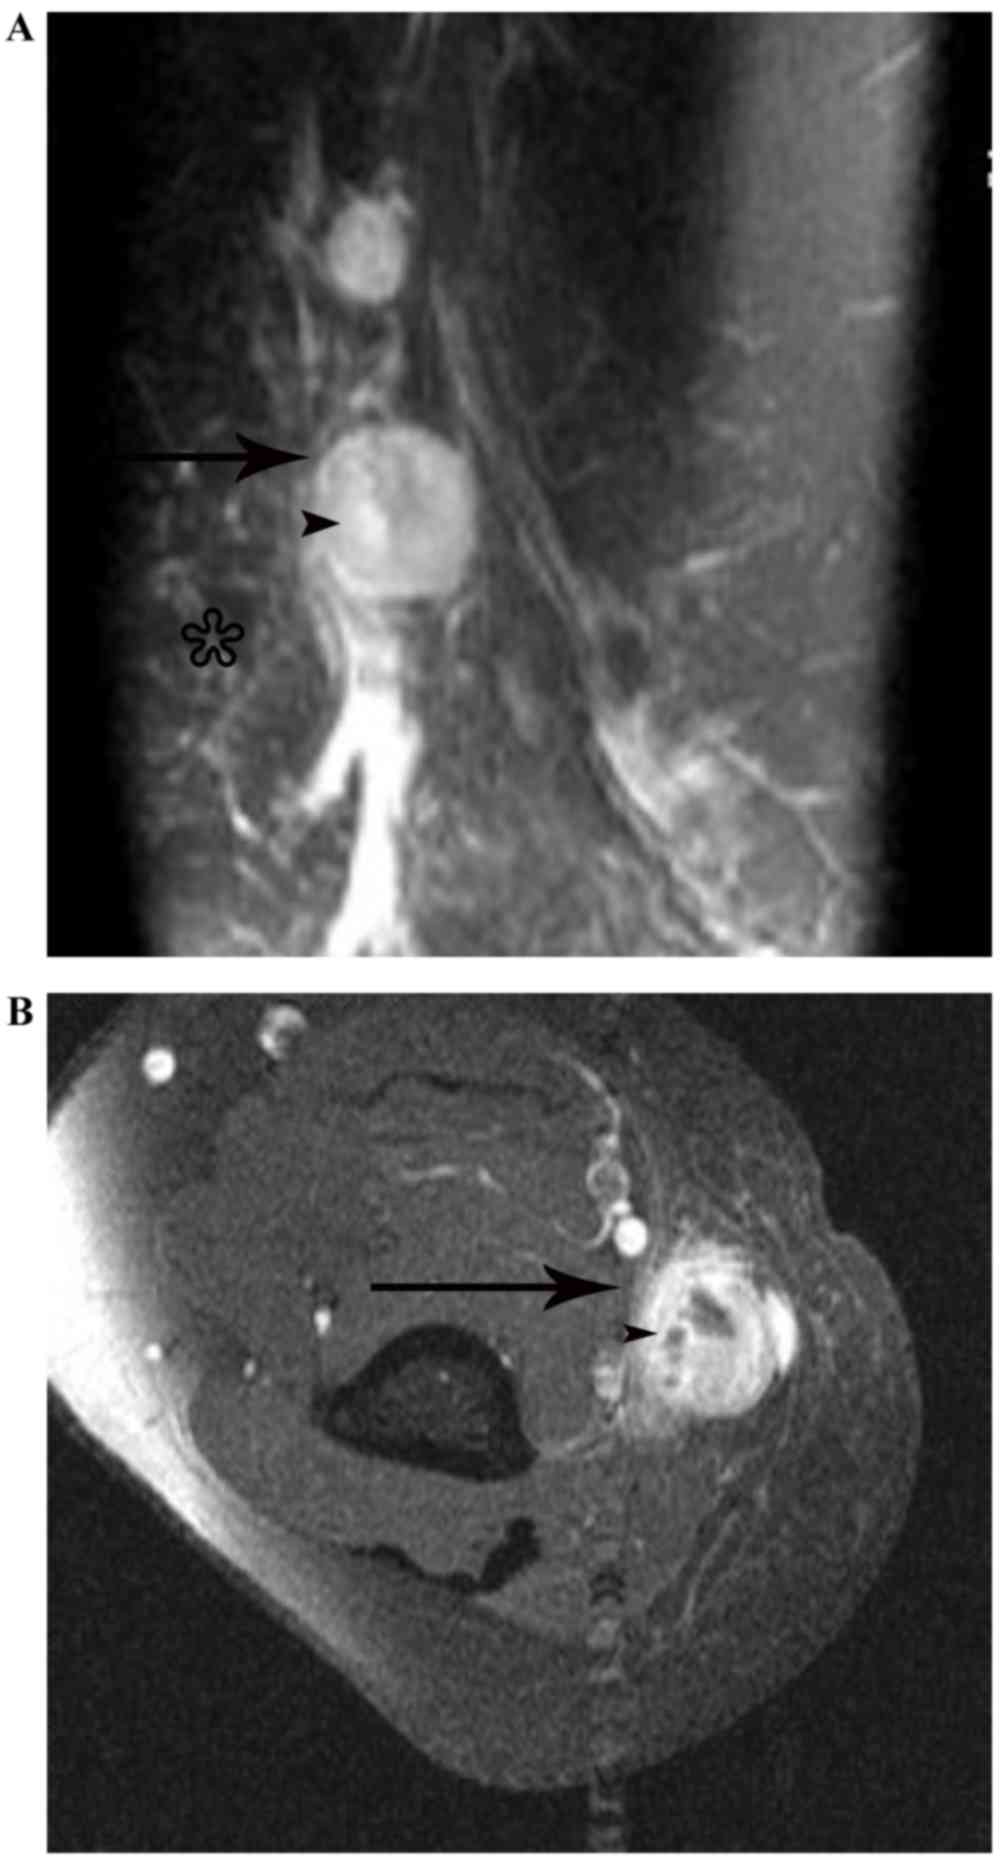

On the MRI scans, all the 14 nodes identified were homogeneously or heterogeneously isointense to muscle or with slightly increased intensity compared with that of muscle on T1WI, and homogeneously or heterogeneously hyperintense on fat-suppressed T2WI. Subsequent to enhancement, 8 of the 14 nodes displayed moderately homogeneous enhancement with no necrotic areas (Fig. 2) and 2 of the 14 nodes demonstrated marked heterogeneous enhancement with no enhancement of the necrotic central areas, which demonstrated patchy hypointense on T1WI and patchy hyperintense on T2WI in the center (Fig. 3A-C). Another 2 of the 14 nodes exhibited heterogeneous enhancement with marked enhancement of the astral hypointense area on T1WI and T2WI (Fig. 4A-C), and the other 2 exhibited heterogeneous enhancement with marginal petaloid enhancement of the astral hypointense area, namely the ‘rose flower’ sign (Fig. 5A-C). In addition, all 10 cases demonstrated general subcutaneous edema in the vicinity of the nodes.

Figure 4.

Lymphadenopathy in an 18-year-old man with cat-scratch disease at the late stage in the left elbow. (A) The node (arrow) exhibits heterogeneous isointensity to muscle with astral hypointensity (arrowhead) on T1WI, and (B) heterogeneous hyperintensity with astral hypointensity (arrowhead) on fat-suppressed T2WI, with general subcutaneous edema (star) in the vicinity of the node. (C) Following enhancement, the node (black arrow) exhibits heterogeneous enhancement with marked enhancement of the astral hypointense area (black arrowhead) on an enhanced fat-suppressed axial T1-weighted imaging scan. (D) The two nodes (white arrow) demonstrate heterogeneous enhancement with marked enhancement of the astral hypointense area (white arrowhead) on an enhanced fat-suppressed coronal T1-weighted imaging scan.